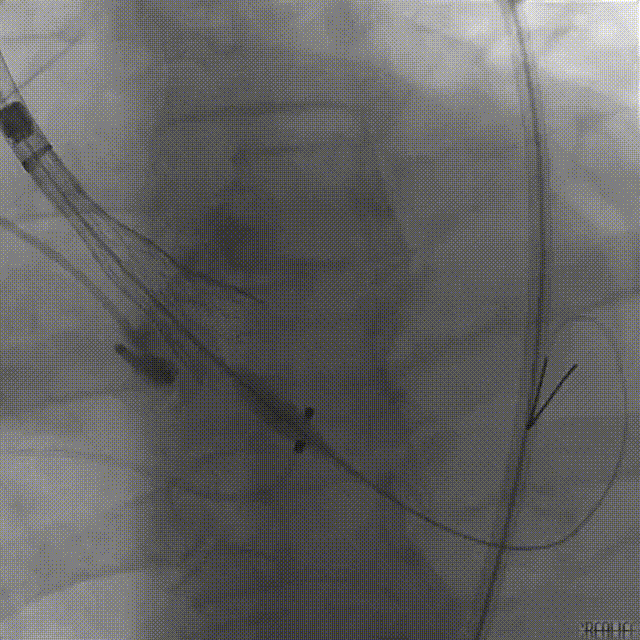

手术采用全麻配合食道超声,经右侧股动脉为主入路,得益于术者丰富经验,配合Evolut PRO优良的过弓性能及精准的器械跟踪性能,瓣膜系统很快到达预期位置。

球囊预扩张

递送到达释放位

因患者自身主动脉根部结构特殊,导致定位困难:严重的钙化灶使得猪尾导管很难送至窦底;但凭借Evolut PRO稳定的多次可回收功能,术者通过对瓣膜的回收及再释放,最终找到最佳释放位置,获得最佳疗效。

瓣膜释放

评估

释放后造影